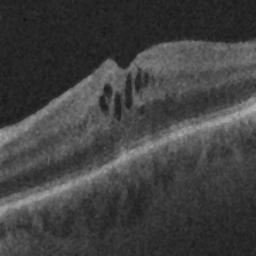

The qualitative results of the proposed system is shown in the Fig. 3. The detection task is evaluated using Area Under the Curve(AUC) metric and the segmentation task is evaluated using Dice Coefficient(DC) metric and the results are presented in Table1

| (a) De-noised OCT slice | (b)Predicted fluid region | (c)Manual fluid segmentation |

| (d) De-noised OCT slice | (e)Predicted fluid region | (f)Manual fluid segmentation |

| (g) De-noised OCT slice | (h)Predicted fluid region | (i)Manual fluid segmentation |

| (j) De-noised OCT slice | (k)Predicted fluid region | (l)Manual fluid segmentation |

| (m) De-noised OCT slice | (n)Predicted fluid region | (o)Manual fluid segmentation |